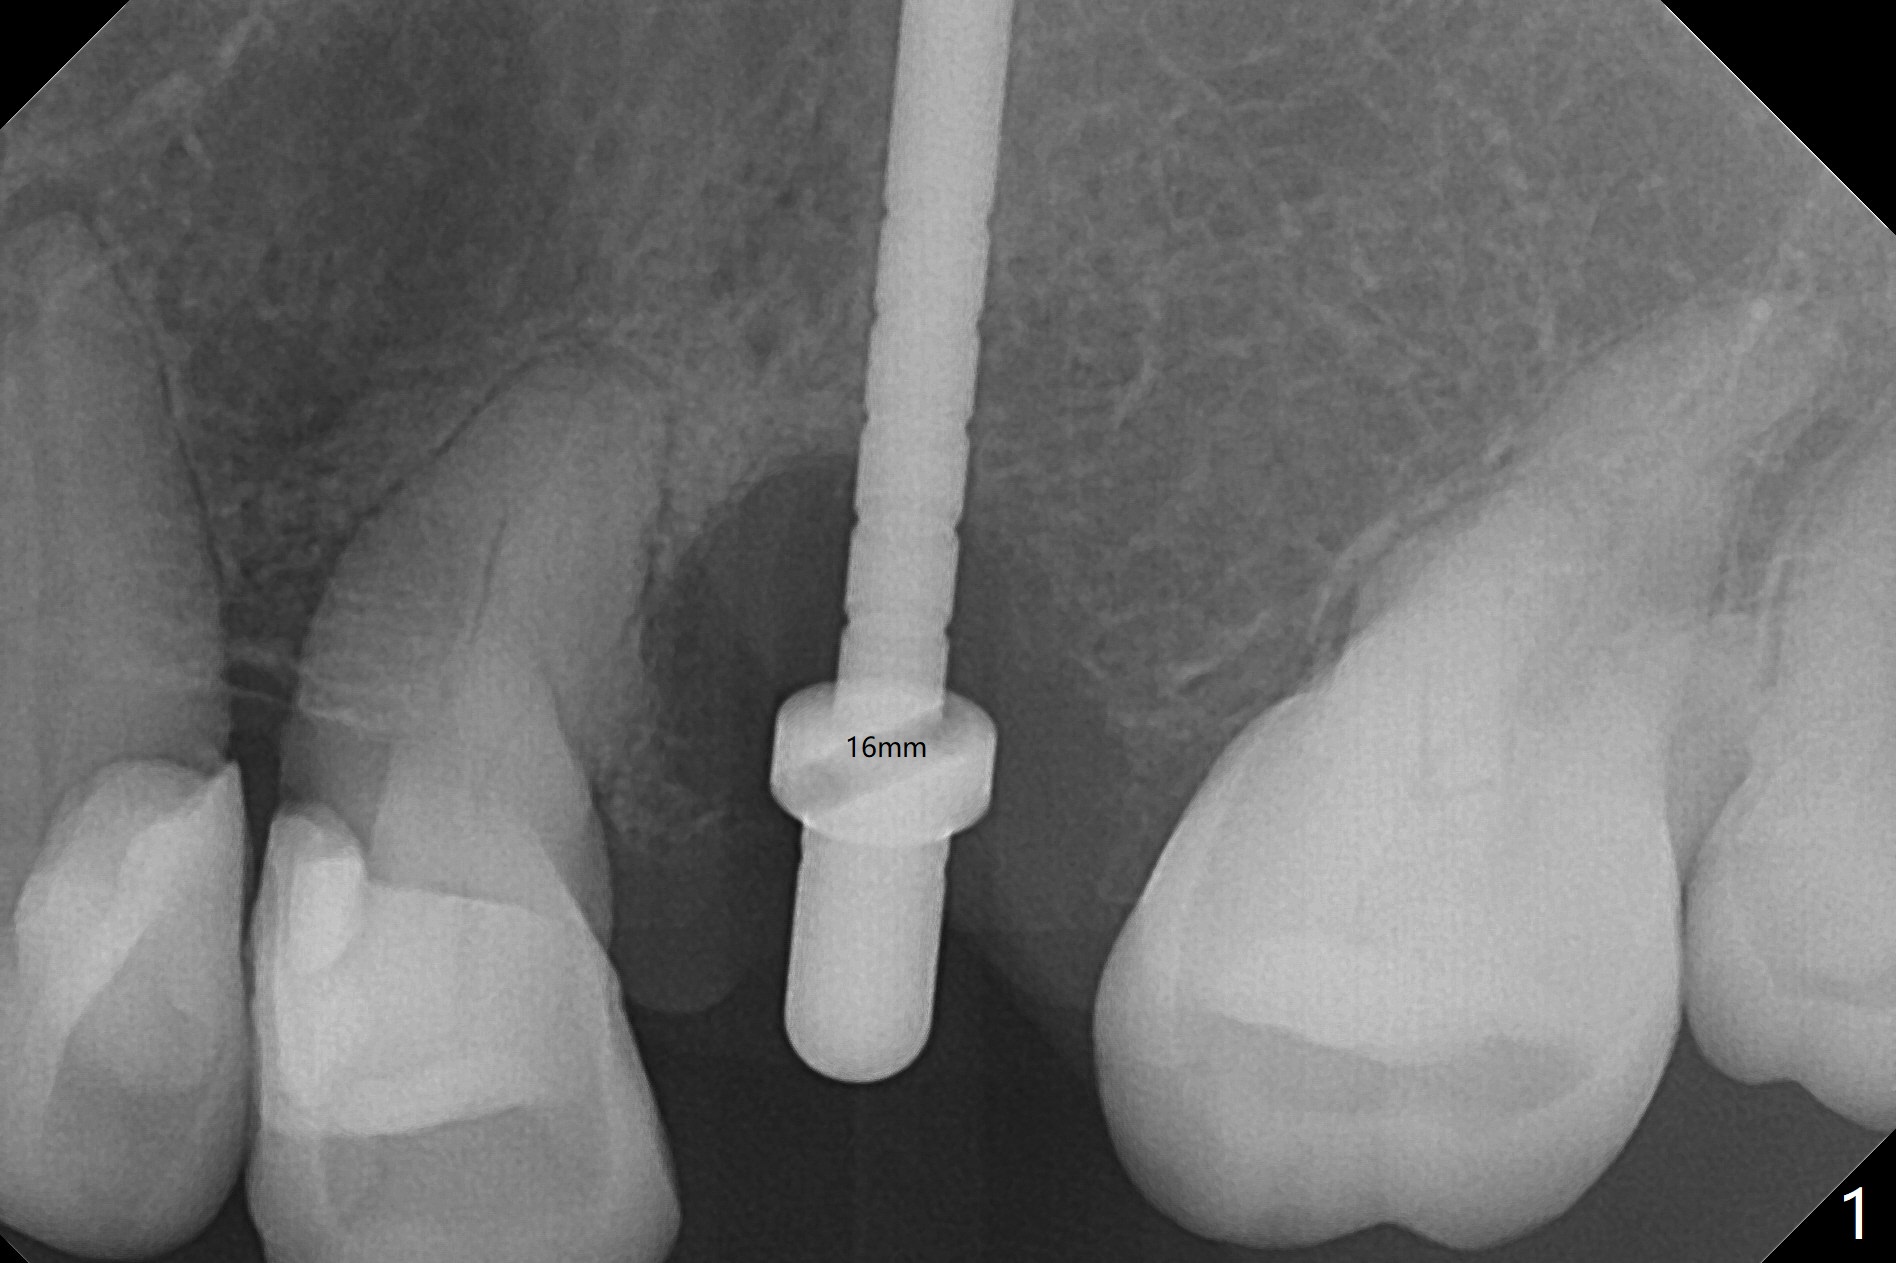

When a 2x16 mm parallel pin is inserted at #13 after extraction, PA does not show the upper end, as related to the long bone (Fig.1). In spite of underprep osteotomy, a 3.8x18 mm implant achieves ~ 20 Ncm of insertion torque (Fig.2). The long implant is still in the lower half of the triangular (cone-shaped) bone (Fig.3 red dashed line) between the nasal cavity (N) and the maxillary sinus (S). The bone is also wide. When a 4.5x5(5) mm abutment is placed, it is buccal. It appears that an angled abutment is needed for final restoration (probably 4.5x15 or 25 degrees, 5 mm cuff). When an angled abutment is placed 1 month posotp, the implant is found unstable. A healing abutment is placed (5.5x7 mm). Progressive loading is initiated 4-5 months postop. The implant becomes stable nearly 5 months postop (Fig.4), but the buccal gingiva is erythematous and tender, probably due to infected bone graft (one large piece), which is removed. One week later, the gingiva looks normal; impression is taken (Fig.5).